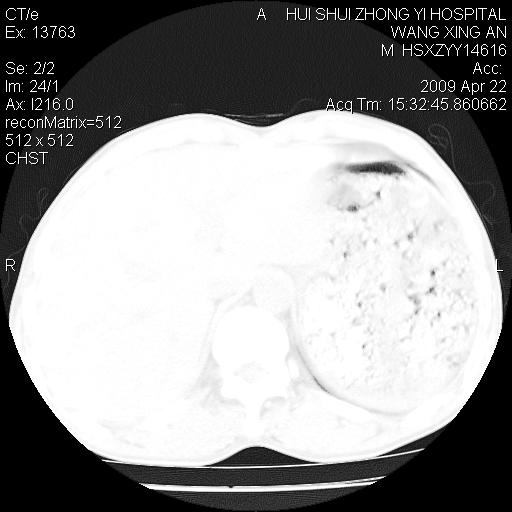

标题: CT19534:患者男、46岁咳嗽、胸痛半月。 [打印本页]

标题: CT19534:患者男、46岁咳嗽、胸痛半月。

1、右下肺中央型肺癌并右肺转移,右肺下叶不张。(肿块围绕右肺下叶支气管生长,致管腔闭塞右肺下叶不张;右肺有结节影)。

2、右侧胸腔积液。

3、右中上肺陈旧性肺结核(右肺见纤维化病灶及点状钙化)。

1、右下肺中央型肺癌并右肺转移,右肺中下叶不张。(右肺有结节影)。胸骨转移

2、右中上肺陈旧性肺结核(因为大多为纤维灶)。

3、右侧胸腔积液。

1)右肺中间段支气管癌并右肺下叶肺不张。2)右肺上叶、两肺下叶背段感染性病变。3)右侧少量胸腔积液。